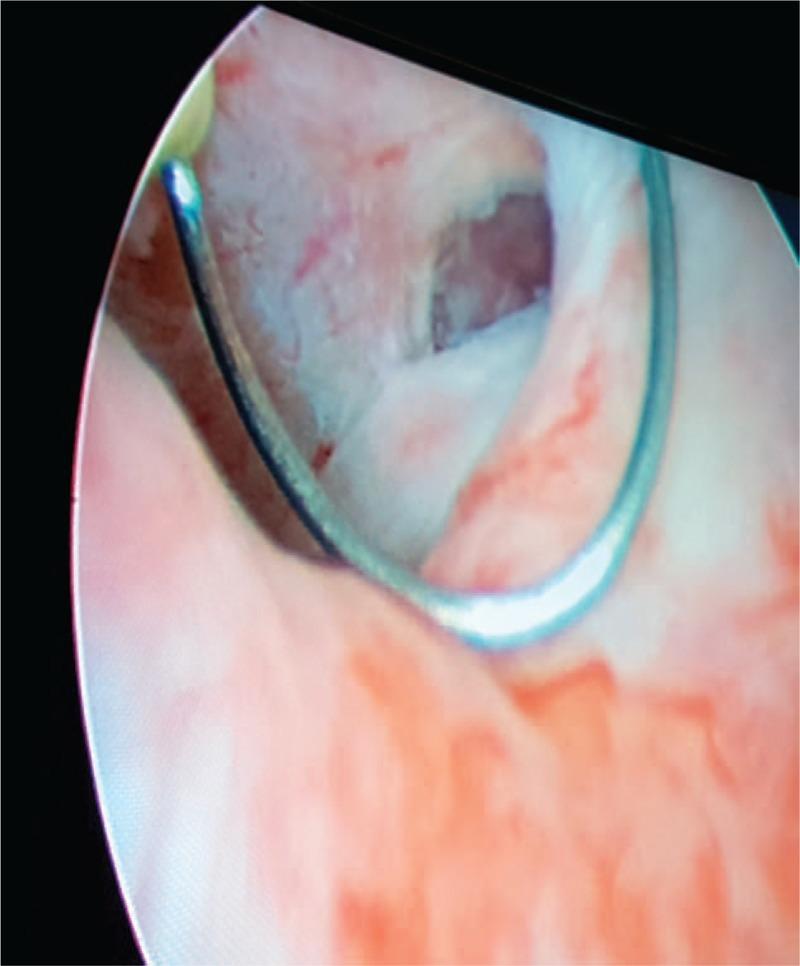

CT scan showed hypertrophy of the right hypogastric artery with severe vascular malformations: the right pudendal artery was massively dilated with early visualization of venous drainage without evidence of arteriovenous fistulae; regular bulbocavernous capillary blush; right upper gluteus artery hypertrophic and dilated. Multiple twisting and aneurysms of the right internal pudenda artery were bleeding from multiple points. Cystoscopy showed a fistula between the proximal urethra and the penoscrotal dartos. Coagulation tests revealed the presence of factor XIII deficiency INTERVENTIONS:: The patient underwent several procedures including percutaneous scleroembolization of the internal pudendal arteries, removal of the penile implant, recombinant factor XIII (FXIII) administration, and cord blood platelet gel application.

CT扫描显示右下腹动脉肥大并伴有严重血管畸形:右侧阴部动脉大量扩张,早期可见静脉引流,无动静脉瘘证据;球海绵体毛细血管造影正常;右上臀动脉肥大扩张。右侧阴部内动脉多处扭曲和动脉瘤出血。膀胱镜检查显示近端尿道与阴茎阴囊肉膜之间存在瘘管。凝血试验显示存在因子XIII缺乏。